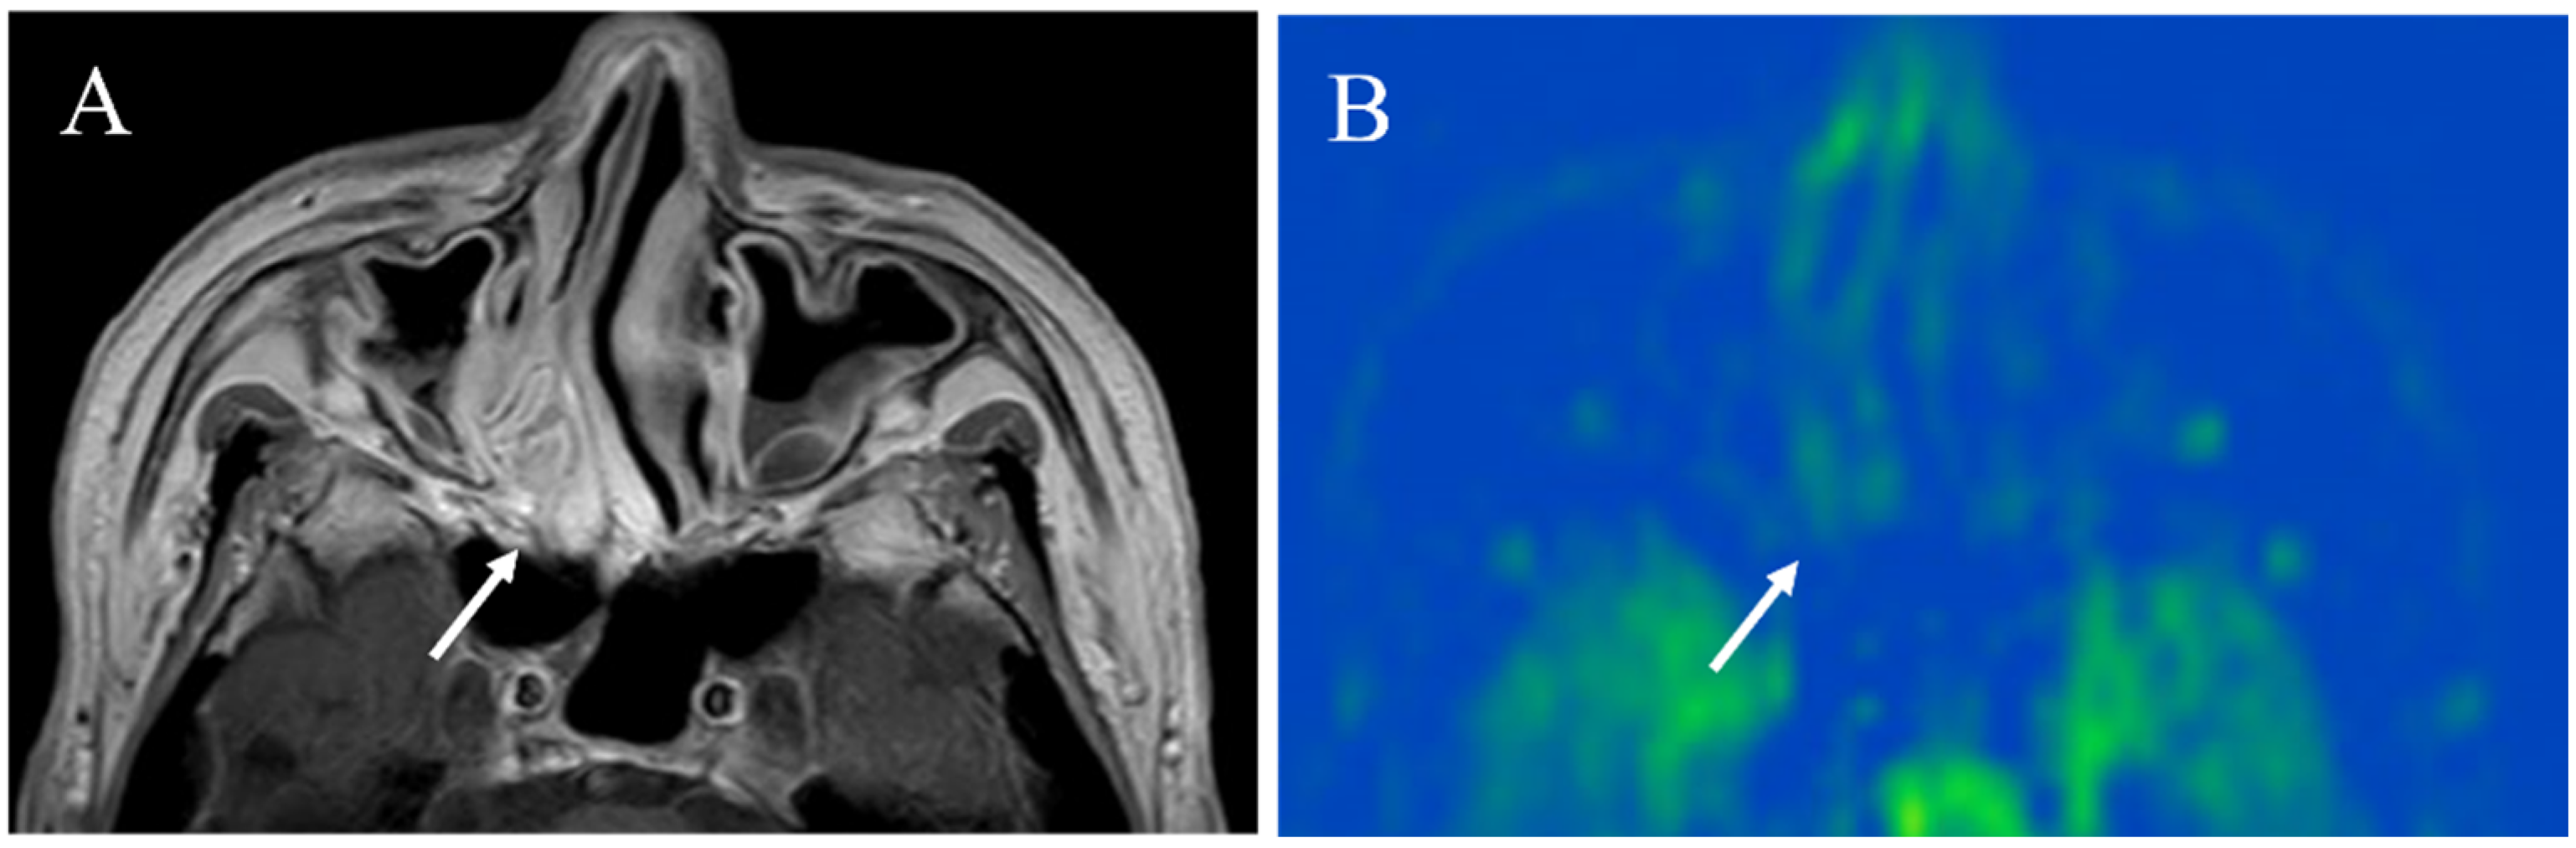

5.1.1. Inflammatory Lesions: Sialadenitis and Dacryoadenitis

5.1.2. Hypervascular Lesions